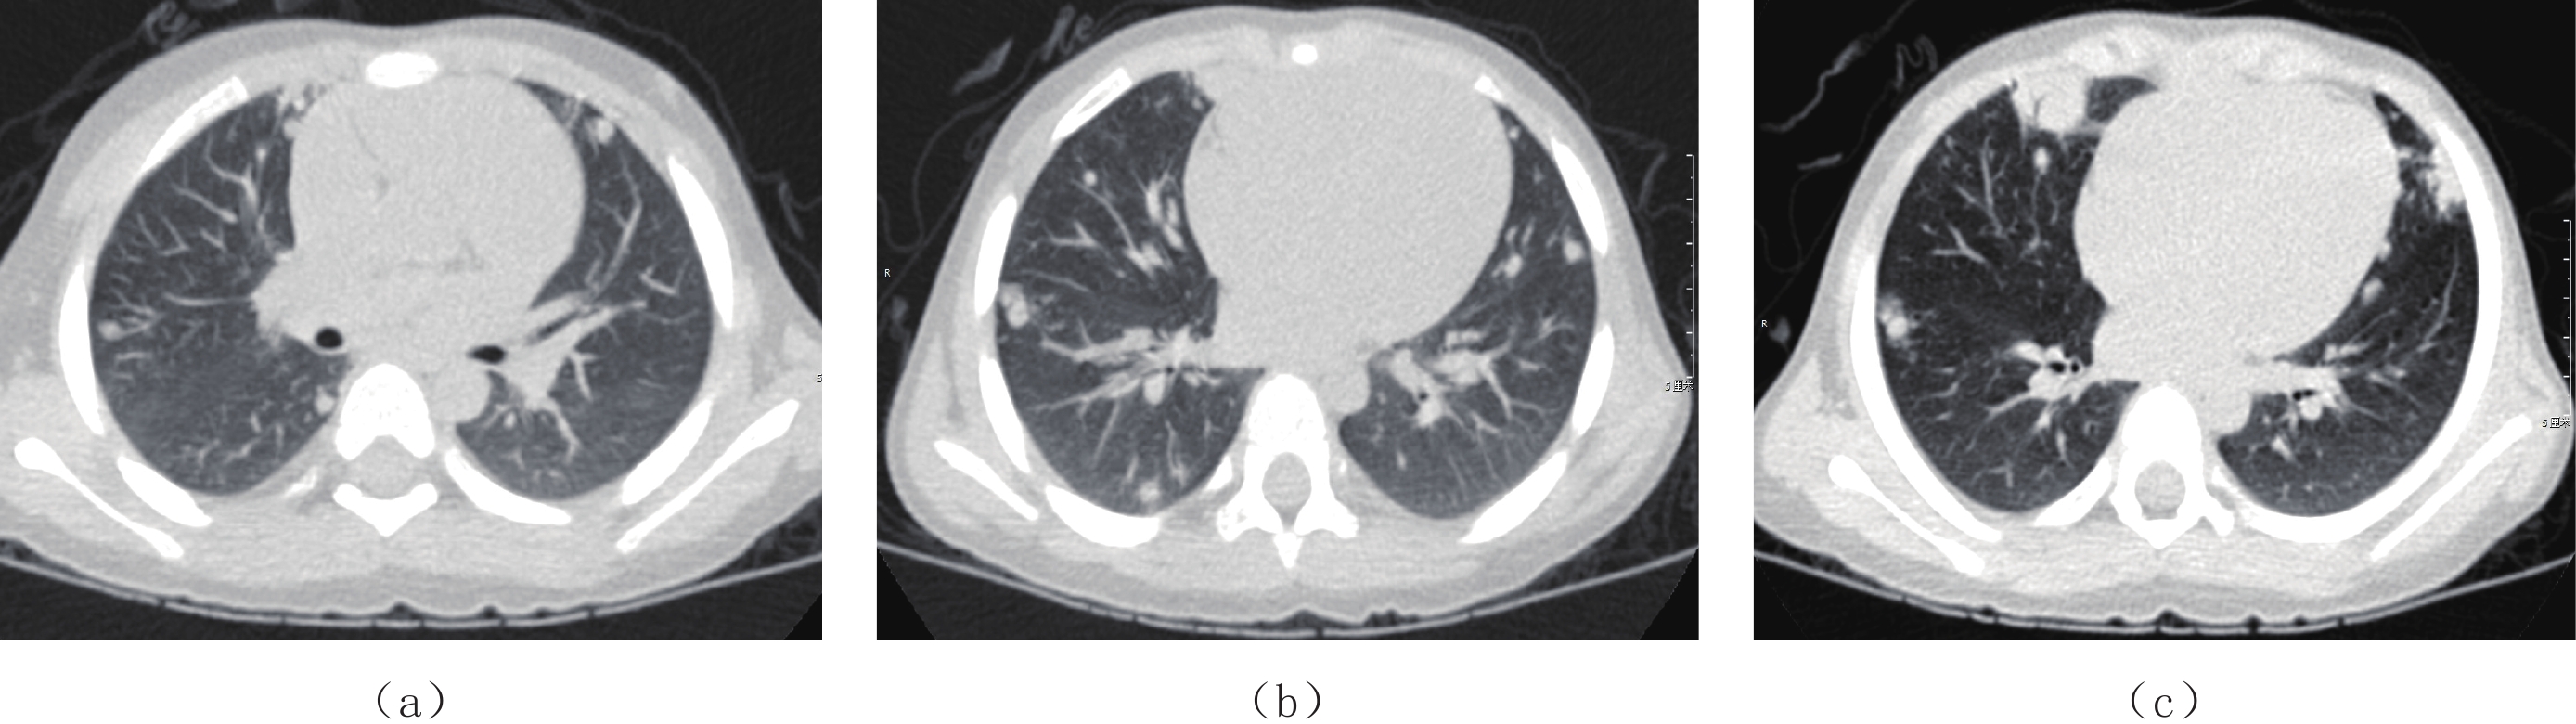

Epstein-Barr virus (EBV), also known as a gamma herpesviru, has the characteristics of lymphophilic tissue. EBV is one of the most common human viruses of the human cold virus group and the first human tumor virus found. Infection with EBV occurs by the oral transfer of saliva and respiratory secretions. Human B-lymphocytes and epithelial cells are EBV-susceptible host cells. First EBV infection often occurs in infancy and in childhood. EBV-associated diseases include infectious mononucleosis, EB virus associated hemophagocytic lymphoproliferative disorder (EBV-HLH), chronic active EBV Infection, EBV infection-associated autoimmune disease. EBV infection can also cause the proliferative diseases of the infected cells, such as various non-malignant lymphoproliferative diseases, lymphomatoid granulomatosis, EBV associated with many more malignant diseases including Burkitt′s lymphoma, Hodgkin′s lymphoma, Diffuse Large B-Cell Lymphoma, NK/T cell lymphoma, nasopharyngeal carcinoma, a subset of gastric carcinomas, and many more. This paper mainly focuses on EBV associated lymphoproliferative diseases and imaging characteristics in children.